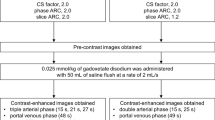

Plethysmographic excursion derived from k-space data

The computation of the plethysmographic maps from the GRASP sequence was performed with a soft-gating algorithm implemented in MATLAB (DICOM and Statistics Toolbox Release 2017b, The MathWorks). While the normal image reconstruction relies on multiple spokes combined into a single imaging frame per time point, k-space evaluation for diaphragmatic motion detection evaluated every change of k-space through the addition of individual new spokes throughout the entire imaging interval, resulting in a temporal resolution of 0.19 s for each updated map. Plethysmographic maps were combined into normalized respirational curves. The k-space evaluation technique and normalization procedure were performed analogously to the description in [13] (Fig. 2).

Superposed infographic map summarizing the cardiovascular contrast dynamic, the hepatic translational activities, and the diaphragmatic plethysmography during the contrast-enhanced MRI of the liver following administration of gadoxetate (a) and gadoterate (b), in two different patients. The relative cardiovascular intensity values normalized based on the initial 20-s acquisition extracted from right-ventricular (dark red), left-ventricular (red), and aortic (light red) ROIs plotted over time allow individual definition of eight time points throughout the election cycle (upper graph); temporal evolution is 1 s. The relative hepatic intensity values were derived from the hepatic ROI (green), plotted over time; temporal resolution is 1 s. A hepatic displacement implying a transient respiratory motion beyond normal breathing motion was considered to be significant when a variation of the signal intensity of at least two standard deviations from the baseline was observed. The extracted plethysmographic curve (gray) with a temporal resolution of 0.19 s is superimposed onto the hepatic intensity curve (lower graph). Pronounced respiratory irregularity is seen during the early arterial contrast phase for gadoxetate (a) and during the peripheral venous phase for gadoterate (b), both resulting in extensive hepatic translational movement. Transient respiratory motion occurring after administration of gadoterate (b) is outside the acquisition window for arterial phase MR imaging (black box) while gadoxetate (a) administration leads to motion during the crucial early arterial MR imaging phase

The resulting normalized plethysmographic curves were employed to detect respiratory motion following the administration of contrast material. Significant motion was defined as a variation of the duration from the maximum-to-maximum inspiration of at least two standard deviations from baseline (2 × 0.6482 s), over an interval of at least two breathing cycles. Examinations without detectable variation in respiration during these initial imaging phases were not further analyzed in this study (Fig. 1, Table 1).

Evaluation of cardiovascular contrast dynamics

Each four-dimensional dataset was loaded into the software application and reformatted into the axial and coronal image planes. Three regions-of-interest (ROIs) were placed manually: within the central right and left ventricles, and within the lumen of the abdominal aorta immediately upstream from the origin of the celiac trunk. The resulting intensity values were normalized and plotted over time as presented in Fig. 2. These cardiovascular intensity curves resulted in eight intra-individually defined contrast phases: Tbaseline (first 20 s of the acquisition), Tperipheral-venous (peripheral-venous distribution starting at the 20-s mark until right-ventricular maximum intensity), Tpulmonary (pulmonary distribution ranging from right-ventricular to left-ventricular intensity maxima), Taortic (aortic distribution ranging from left-ventricular to aortic maxima), Tearly-arterial and Tlate-arterial (hepatic arterial parenchymal distribution during two consecutive 20-s intervals starting at maximum aortic intensity), Tportal venous (portal venous parenchymal distribution from 40 to 90 s after maximum aortic intensity), and finally Tdelayed (contrast distribution from 90 s after maximum aortic intensity up to the end of the acquisition). The first four contrast phases will be referred to as the pre-bolus phase.

Evaluation of respiratory-induced translation of the liver

Each four-dimensional image set was reformatted to the coronal plane for evaluation of hepatic cranio-caudal translation due to respiration. A crescent-shaped polygonal ROI was placed just below the diaphragm within hepatic segment VIII during expiration-induced buckling of the right diaphragm. The intensity values were normalized and plotted over time. Hepatic translation was represented by decreasing signal intensities as seen in Fig. 2.

Hepatic displacement implying a transient respiratory motion was quantified with respect to (1) its duration from onset to peak inspiration—acme—(2), its onset timepoint, and (3) its acme timepoint. Values for (2) and (3) were measured in reference to the right-ventricular contrast arrival and the peak aortic enhancement, respectively. The onset of the hepatic displacement was determined by a negative downslope of the intensity curve over at least five measured time points below the baseline.